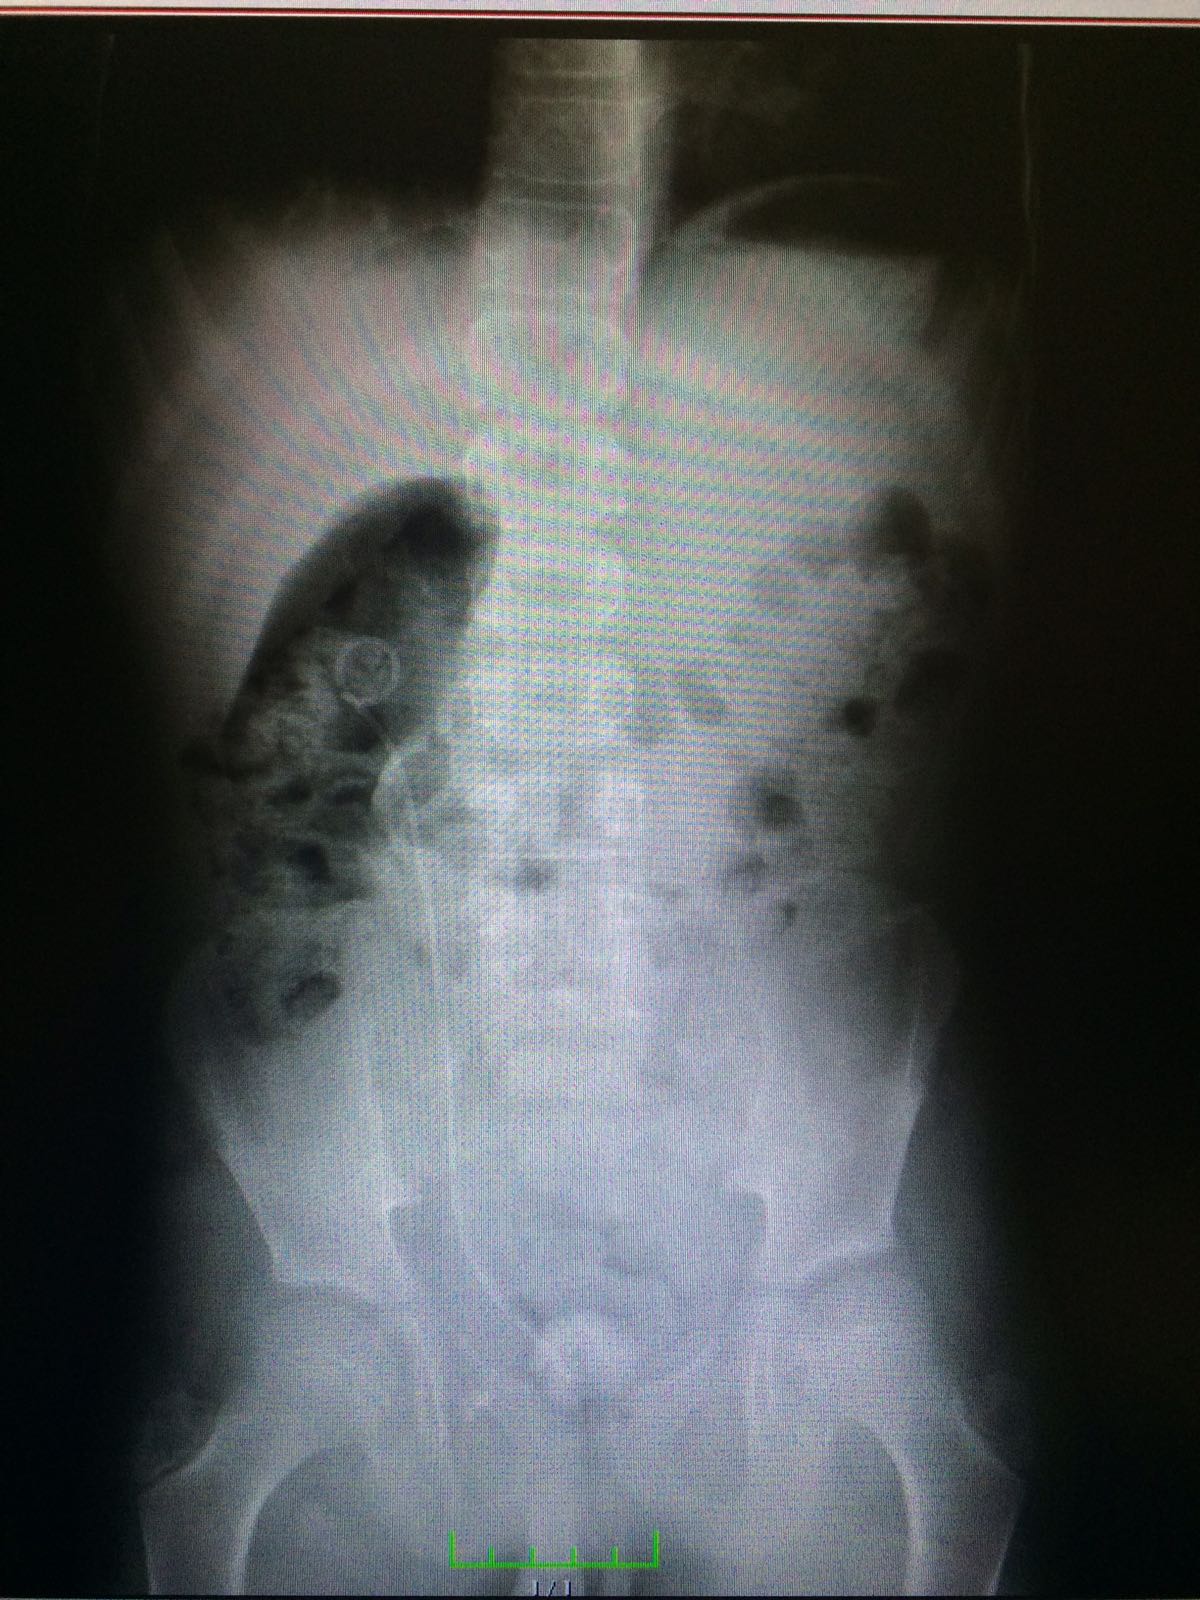

The Miniaturization of Instruments and Laser Lithotripsy have Improved Urolithiasis Treatment without Requiring Fluoroscopic Control in Preschool Children

Fazlı Polat, Zafer Turkyilmaz, Ramazan Karabulut, Suleyman Yesil, Kaan Sonmez